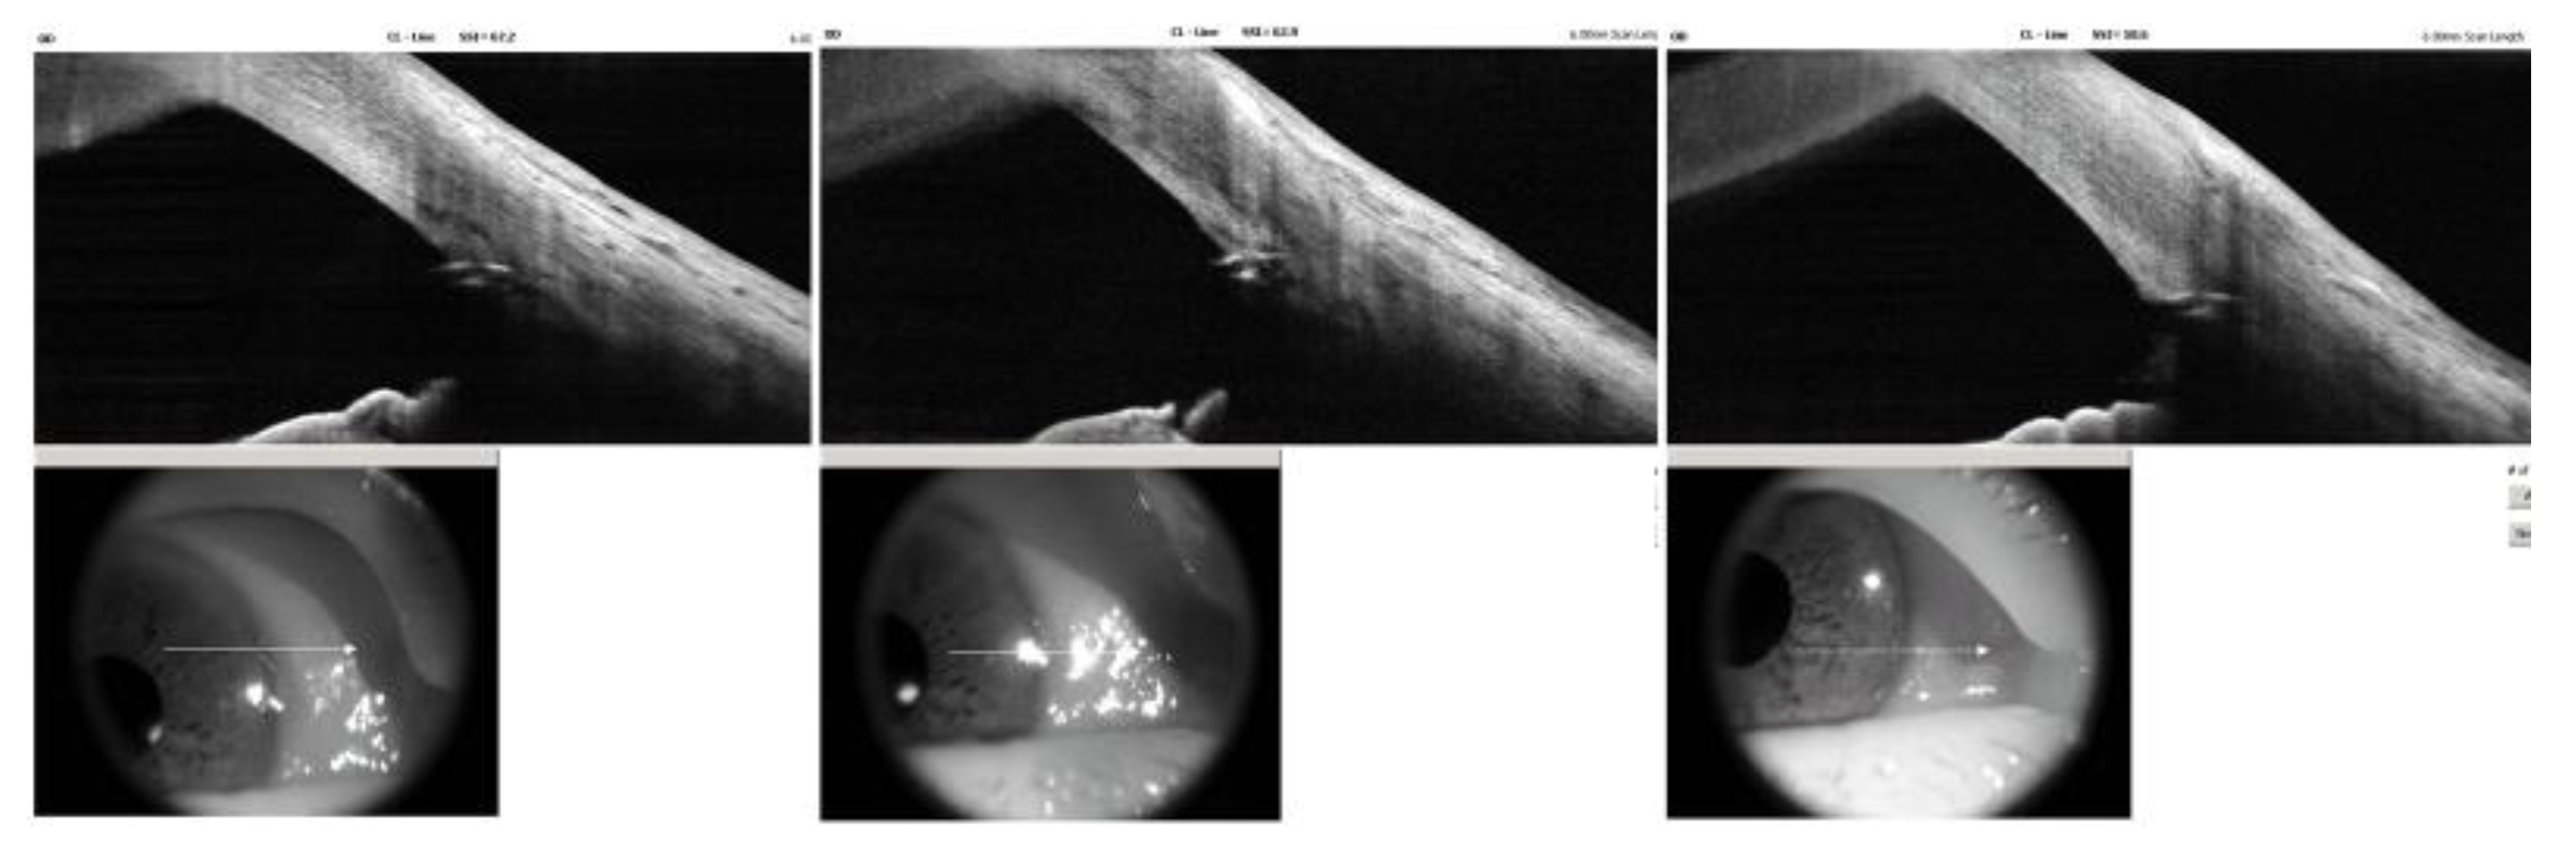

Based on these findings, the mechanism of IOP increase was assumed to be due to steroid-induced TM dysfunction with increased trabecular outflow resistance. To re-establish physiologic aqueous outflow via the Schlemm’s canal, iStent infinite implantation was planned. The procedure was performed under topical anesthesia using a clear corneal incision. Three trabecular micro-bypass stents were implanted sequentially into the nasal quadrant under direct gonioscopic visualization. Postoperatively, good positioning of all three stents within the pigmented TM without significant inflammation or hyphema were observed on slit lamp examination (Figure 3). AS-OCT demonstrated similar findings except for one slightly over-implanted stent in the inferonasal side. (Figure 4).

Figure 3. Postoperative slit lamp photographs and gonioscopic findings. The three stents are clearly visible within the pigmented trabecular meshwork on indirect gonioscopy. The anterior chamber is quiet, with neither inflammation, peripheral anterior synechiae, nor stent obstruction.

Figure 4. Postoperative anterior segment optical coherence tomography (AS-OCT) for iStent infinite position. AS-OCT scans show three iStent infinite trabecular microbypass stents (upper panels) placed along the nasal quadrant. The lowest stent appears slightly over-implanted, with its proximal edge minimally recessed into the trabecular plane; however, the device maintains full contact with Schlemm’s canal and is likely functional. The reference infrared reference images from the lower panels indicate scan locations across each stent.